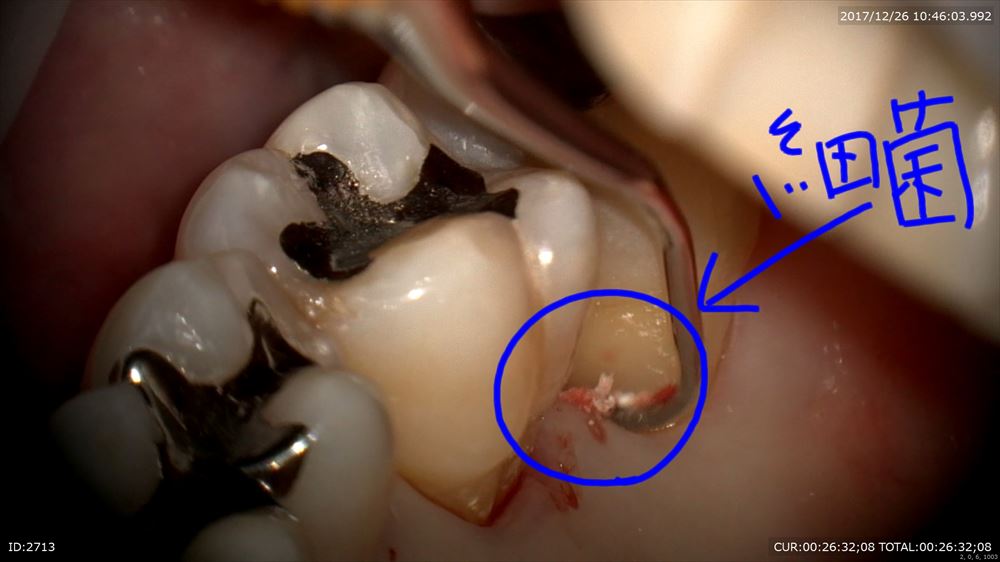

最後は精密根管治療のケース。根管が細くレントゲンでも石灰化が認められました。困った。マイクロスコープで探していきます。

ここまで拡大できました。4つ根っこがあったのです。